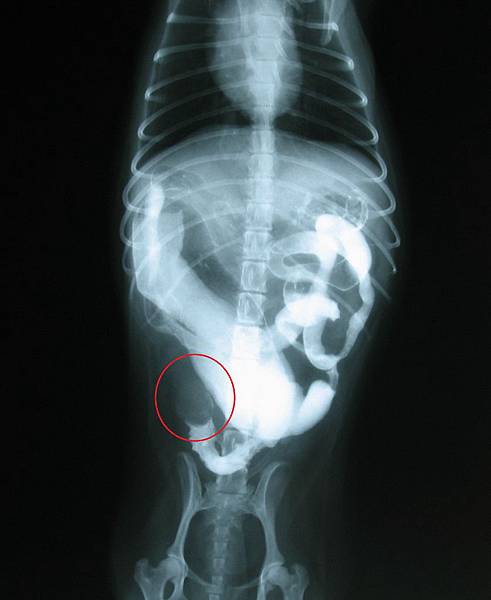

這時就需要進行消化道照影,消化道照影是給

動物食入一種可以在x光下顯影的液體,藉由連續

時間的拍攝,觀察液體在消化道流動的狀況,如果

有異物阻塞,照影劑就會停留在某段消化道,不會

繼續往前移動,如果是部份阻塞,則照影劑在阻塞

的部位會緩慢通過,且會產生異常的影像。

一般攝影下,無法顯影的異物,經過照影,照影劑無法通過(嘉興動物醫院)